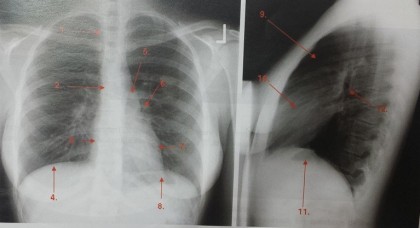

Radioanatomia aparatului respirator

Imaginea radiologică a toracelui este complexă, fiind determinată de structuri anatomice cu capacitate diferită de atenuare a razelor X (exemplu: peretele toracic, aparatul respirator, mediastinul).

În incidența de față traheea se evidențiază pe linia mediană a toracelui, având un traiect descendent, oblic în jos și la dreapta. Lumenul său este uniform înafara amprentei aortice situate pe marginea sa stângă, imediat deasupra bifurcației. Traheea se bifurcă în două bronșii principale la nivelul vertebrei toracale T5, unghiul de deschidere variind între 45 și 70 de grade. Bronșia principală dreaptă are un traiect anterior și vertical comparativ cu bronșia principală stângă.

În incidența de profil, imaginea traheei este bine evidențiată, având traiect oblic în jos și posterior. Bronșia principală dreaptă continuă traiectul traheei, în timp ce bronșia principală stângă (mai orizontală) este evidențiată ca o hipertransparență ovalară, sub crosa aortei și a arterei pulmonare stângi, alcătuind hilul aerian.